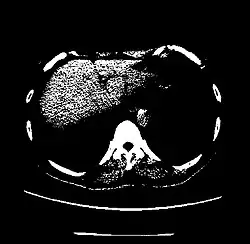

The Hounsfield scale (/ˈhaʊnzfiːld/ HOWNZ-feeld), named after Sir Godfrey Hounsfield, is a quantitative scale for describing radiodensity. It is frequently used in CT scans, where its value is also termed CT number.

| Liver | 60 ± 6[26] | |

A practical application of this is in evaluation of tumors, where, for example, an adrenal tumor with a radiodensity of less than 10 HU is rather fatty in composition and almost certainly a benign adrenal adenoma.[31]